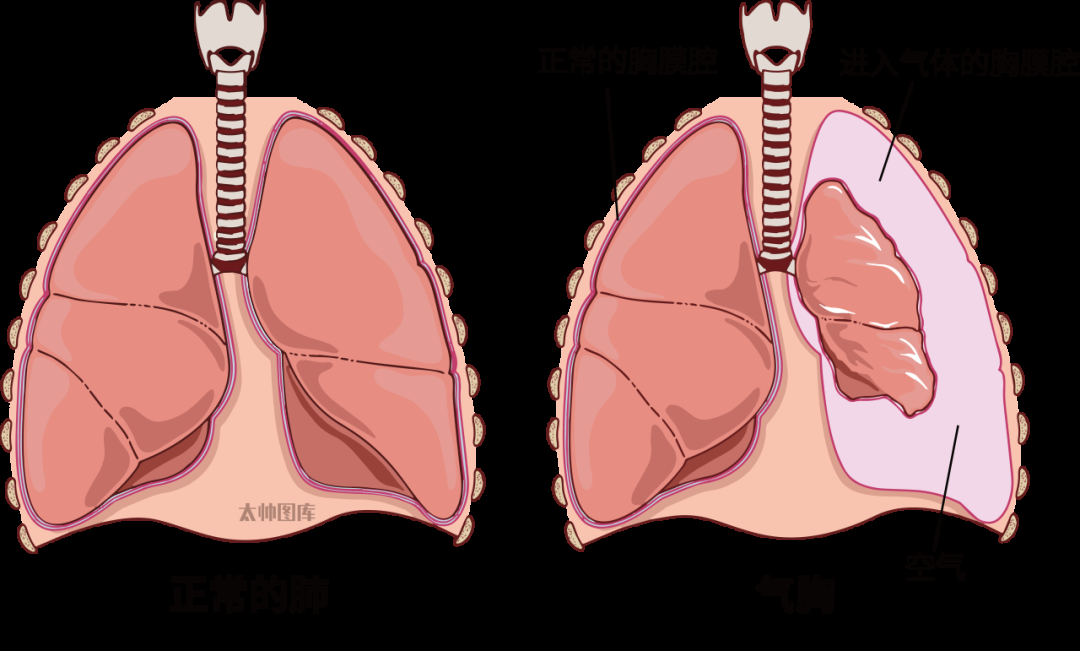

气胸,即胸腔内积气的状态,是由空气进入胸膜腔引起的。造成气胸的原因有多种,主要分为自发性、外伤性和医源性。

自发性气胸最为常见,简单来说,就是肺表面破了个小洞,空气从肺里漏到了胸膜腔(肺和胸壁之间的空隙)。这些漏出来的空气会压迫肺部,让人感觉胸痛、呼吸困难,严重时甚至会危及生命。